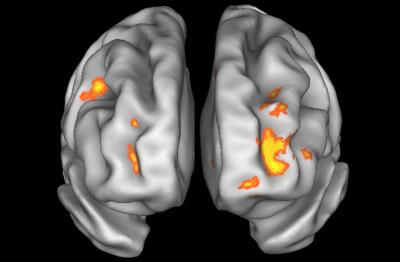

"We found that the brain does a pretty good job at compensating for the effect that alcohol has on the brain's ability to process the visual information needed to adjust motor commands," says John D. Van Horn, a research associate professor of psychological and brain sciences and the lead author on the paper. "Alcohol selectively suppresses the brain areas needed to incorporate new information into subsequent and correct motor function."

For the study, eight people, ranging in age from 21-25, were asked to maneuver a joy stick both while sober and when experiencing a blood alcohol level of 0.07 percent (just below the legal definition of intoxicated). Brain activity during this task was captured using functional magnetic resonance imaging, known as fMRI. The study was published online in the journal NeuroImage on March 6, 2006.

The study found that alcohol selectively suppresses cognitive activity in the frontal and posterior parietal brain regions; these are regions most commonly associated with the brain's ability to monitor and process visuomotor feedback. Van Horn explains that this study is one of the first ever to directly illustrate this suppression effect in the brain in humans using neuroimaging.

"We know that alcohol has a global effect on the brain. This study was unique in that it isolated the specific network that underlies the processing and translation of visual and motor commands. The poor coordination one feels after a couple of drinks is due to the poor feedback processing in brain areas critical for updating the mental models for motor action. While this idea is not entirely new, our demonstration, using functional neuroimaging is a first and likely the start of a more extensive neuroimaging research paradigm into the effects of alcohol on the brain," says Van Horn.